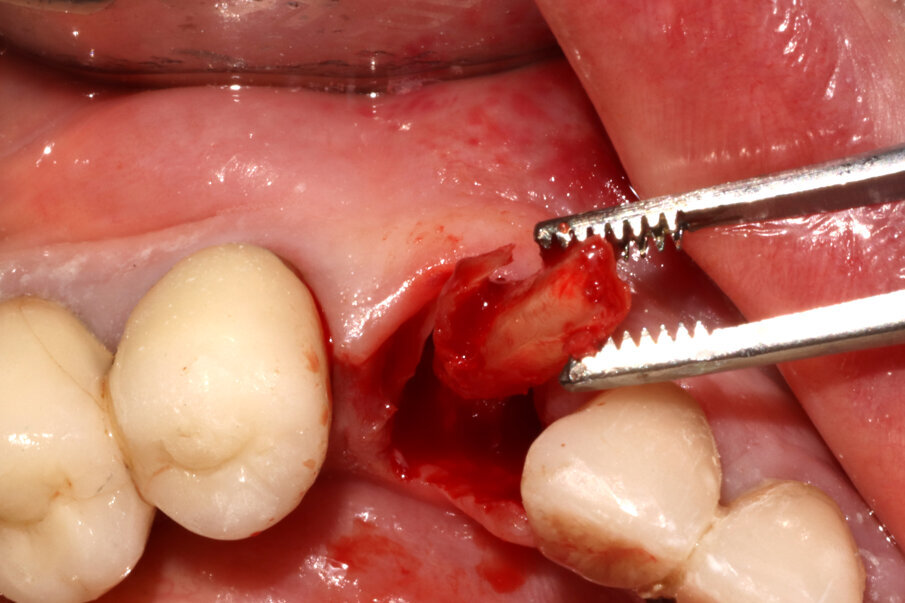

Nature” proposto dalla SISS (Figg. 5-7), che sostanzialmente prevede una decoronazione dell’elemento dentario e un trattamento della radice secondo una direzione crown-down: il canale viene svuotato, la radice raccordata al margine osseo vestibolare, e sezionata in modo da comprendere nella componente rimossa anche l’apice radicolare oltre che la porzione linguale della radice affetta da riassorbimento radicolare. Rimane così una piccola quota di radice vestibolare, spessa circa 1 mm e lunga circa 6 mm, con forma a “C” (per mantenere il legamento parodontale fino ai picchi ossei e mantenere così le papille interdentali). A questo punto viene inserito un impianto Nobel Active 4,3 x 13. Il controllo del posizionamento implantare in ossequio al progetto protesico viene eseguito grazie a un sistema di Chirurgia Navigata (X-Guide, X-Nav Technologies) che ci consente di ottenere una deviazione finale di soli 0,2° (Fig. 8). Una volta inserito l’impianto, lo stesso viene collegato a una torretta provvisoria in titanio sulla quale viene costruito un provvisorio intraoperatorio che rispetti il tragitto transmucoso e non eserciti forze compressive o dislocanti sullo shield vestibolare.

Fig. 12_La porzione di radice linguale correttamente asportata compresa di apice radicolare.